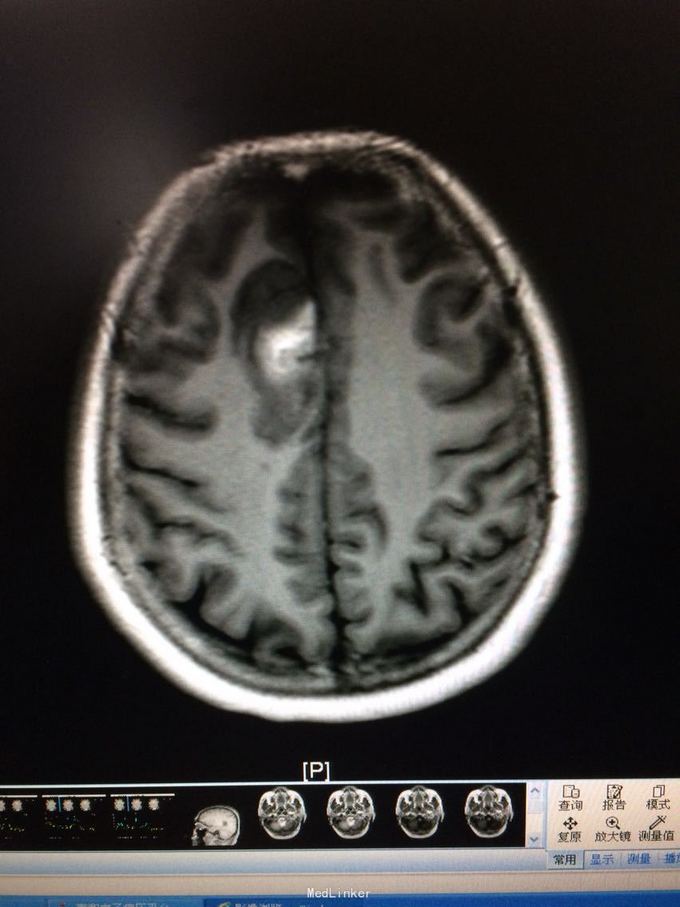

主诉:记忆力减退3月,左侧肢体乏力3天 病史:患者51岁女性,3月前无明显诱因出现记忆力减退,伴头痛,3天前出现站立不稳,左侧肢体乏力,步行困难,当地CT提示右侧额叶低密度灶,

查体:左侧上肢肌力4级,右侧5级,轻瘫试验左侧阳性 辅助检查:右侧额叶、胼胝体膝部病变伴出血,增强扫描明显强化。考虑胶质瘤

诊断:右侧额叶多发脑软化灶 处理:全麻下行右侧额叶占位病变切除术,术后病理提示:符合脑软化,未见明显肿瘤因素等